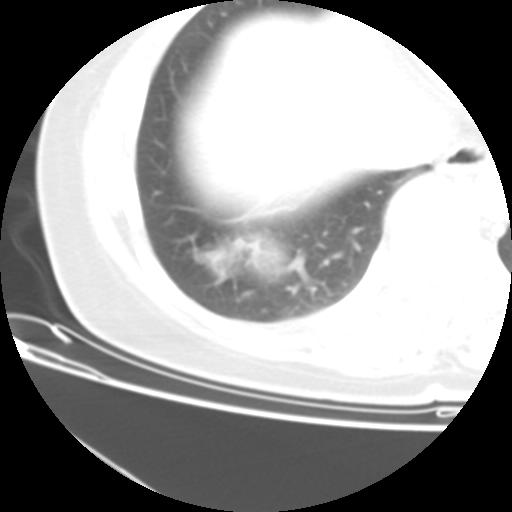

右肺下叶类癌

女 46岁,咳嗽咳血10月

【linyiming】右肺下叶见类圆形软组织影,边缘欠规整,略分叶状。考虑炎症假瘤可能?

未排除周围型肺癌。建议CT增强。

【aosangwa】肺癌的主要特征是:毛刺征、分叶征及胸膜凹陷征,此病例位于右肺下叶距胸膜很近,但没有胸膜凹陷征,其周围像示渗出性病变,病灶在两窗上没有大小没有发生大小改变。

考虑其良性肿瘤,炎性假瘤可能性大,其主要鉴别是:结核球、周围型肺癌、血管瘤

病理诊断类癌(周围型)。